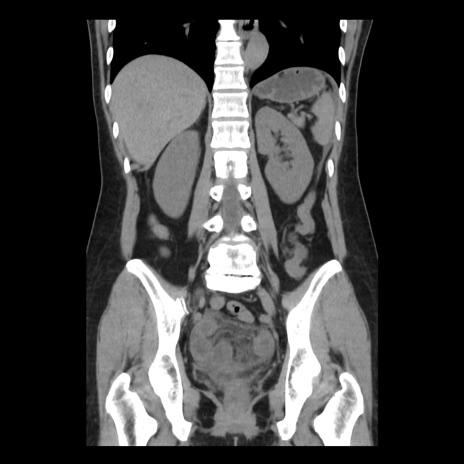

症例10(冠状断像)

【症例】 50歳代女性

【主訴】 腹痛

【現病歴】前日生レバーを食べた。今朝に排便あり。 昼前に突然発症の腹痛を生じ、当院救急外来を受診した。

【既往歴】 子宮筋腫にてで子宮全摘後

【身体所見】 意識清明、腹部:平坦、軟、下腹部やや左を中心に圧痛・反跳痛あり、筋性防御あり

【データ】WBC 7800、CRP 0.07